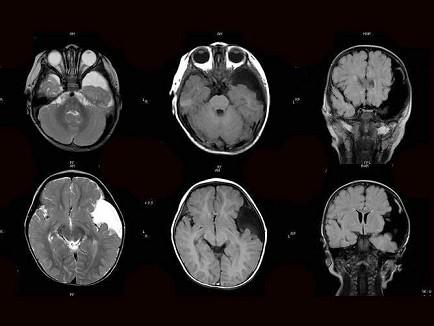

问题 患者,女,1岁半,头颅外伤1天,如图,最可能的诊断为?(?)

选项 A.胶质瘤 B.硬膜下血肿 C.硬膜外血肿 D.脑萎缩 E.蛛网膜囊肿

答案 E